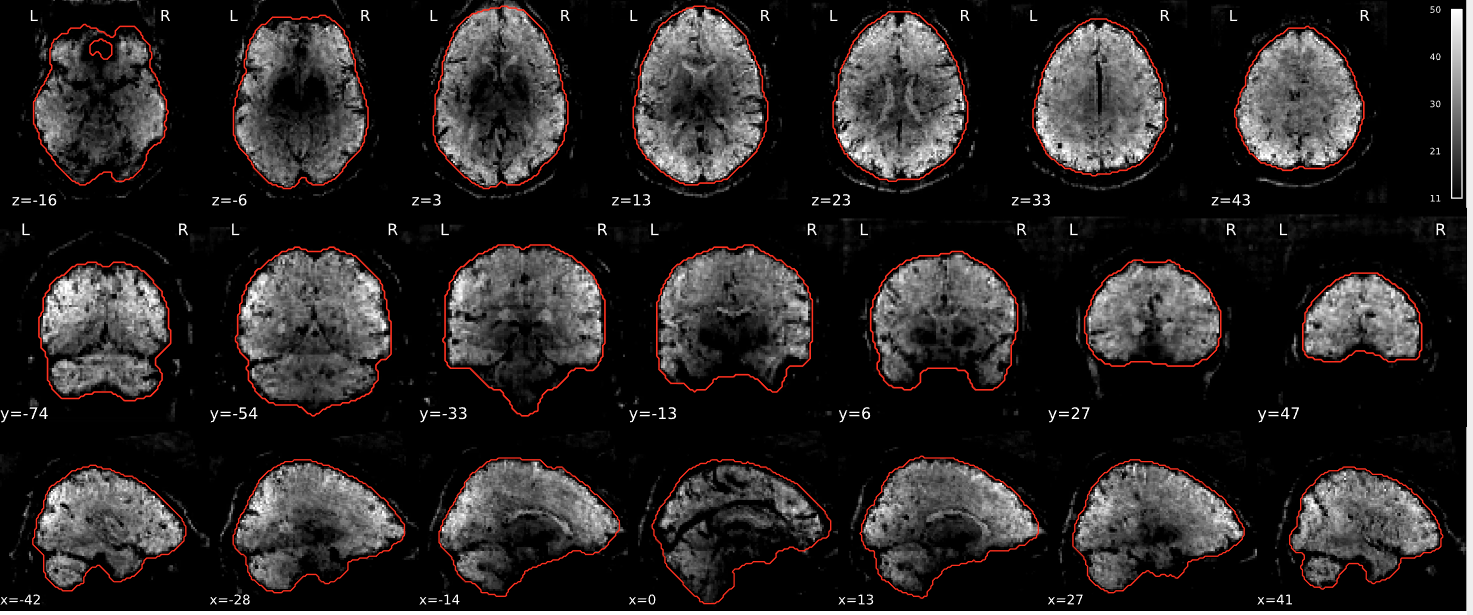

EPI tSNR

In the signal to noise ratio images of the resting state image the desired signal is compared to the amount of background noise. It is important to check all the views (sagittal, coronal, axial) because some artefacts (e.g., stripes) may be evident only in one particular view.

Example of a good subject

- Signal to noise is symmetrically distributed and there is no signal distortion

Example of a bad subject

- Asymmetry

- Potential signal distortion (might represent an artefact)

- Signal drop-out

- Stripes artefact

Clear large artefact (e.g., zebra stripes in example 1) are worth the exclusion of the subject. If you are unsure, check the other quality metrics for that subject to decide whether they should be excluded.

Summary

| good | bad |

|---|---|

| Symmetrical distribution of noise and signal | Asymmetry |

| No disruptions of the signal (no “black patches”) |

Potential signal disruptions (could be related to artefacts) |

| No stripes (sign of high motion) |

Signal drop |

| Stripe artefacts (“zebra” stripes due to motion) |